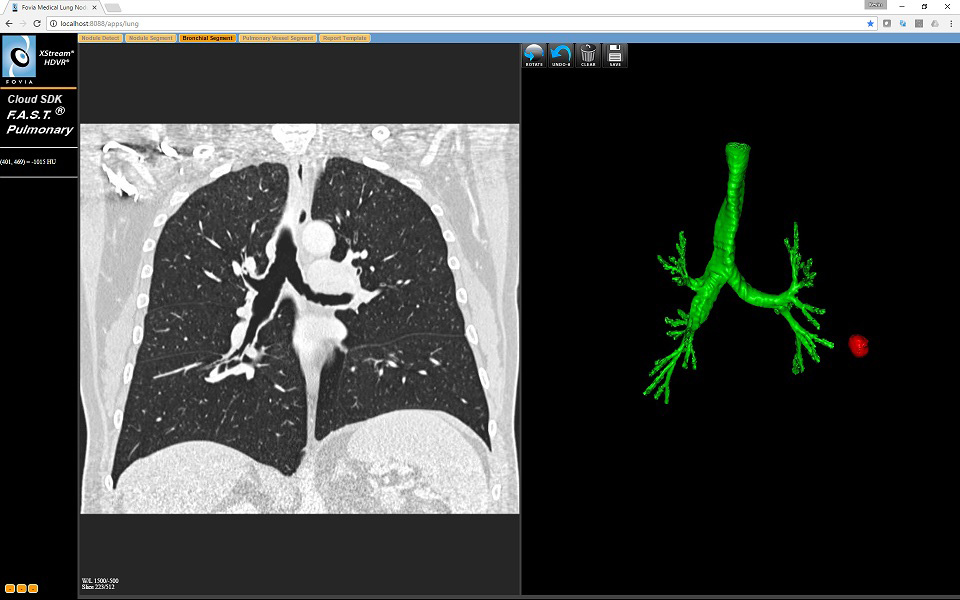

The Bronchial Segment Tab of the application consists of 2

viewports

Left – Sagittal image for selecting start points to segment.

Just like segmenting a nodule, select a point (near the trachea

bifurcation into the left and right bronchial trees) and move the mouse

up and to the right to begin segmenting. You will notice that if yo

move to far to the right, the segmentation "leaks" into the lung tissue

from the bronchial tree. Also if growing too "large" it may also leak,

so finding the optimal point for the two dimensional search (that is

different for each patient) is a difficult time consuming task made

simple, accurate and fast by using interactive segmentation

Right – 3D View with resulting segmentation

The Bronchial Segment Tab of the application consists of 2 viewports